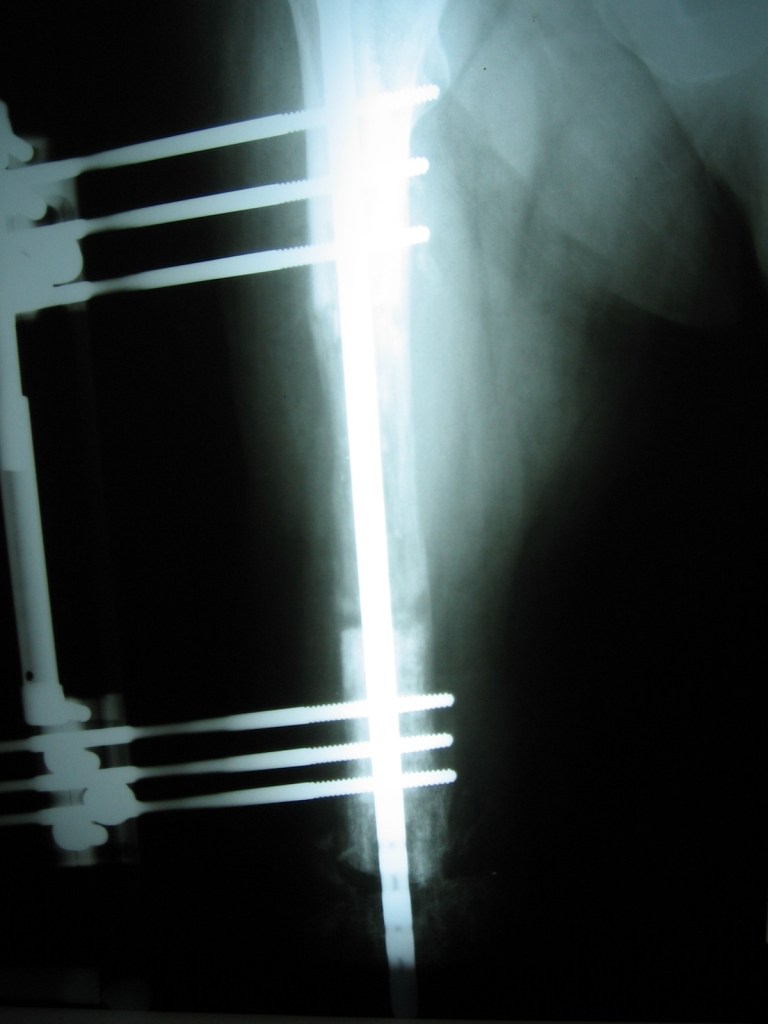

Leonardo Saldaña

tras múltiples cirugías y una osteomielitis grave en mi pierna , la única opción que me daban era la amputación con desarticulación , fue mi hermana quien consulto en Cotram con el Dr Dratewka quien me propuso un tratamiento para tratar la infección y al mismo tiempo reconstruir mi hueso faltante

Tras dos años puedo decir que valió la pena el esfuerzo